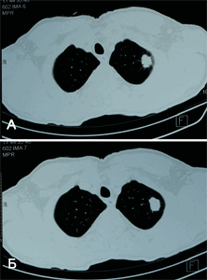

Рис. 2. КТ-картина периферической опухоли левого легкого. В ходе обследования у пациента выявлены множественные метастазы в лимфоузлах средостения, больному было проведено химио-лучевое лечение.

Рис. 5. У пациента К., 65 лет при компьютерной томографии выявлено периферическое образование в верхней доле левого легкого (А, Б). Для окончательной установки диагноза выполнена бронхоскопия с чрезбронхиальной биопсией (В), при которой подтверждена аденокарцинома (злокачественная опухоль) легкого. В марте 2013 года пациент успешно прооперирован в нашем Центре - выполнена расширенная видеоторакоскопическая верхняя лобэктомия слева.